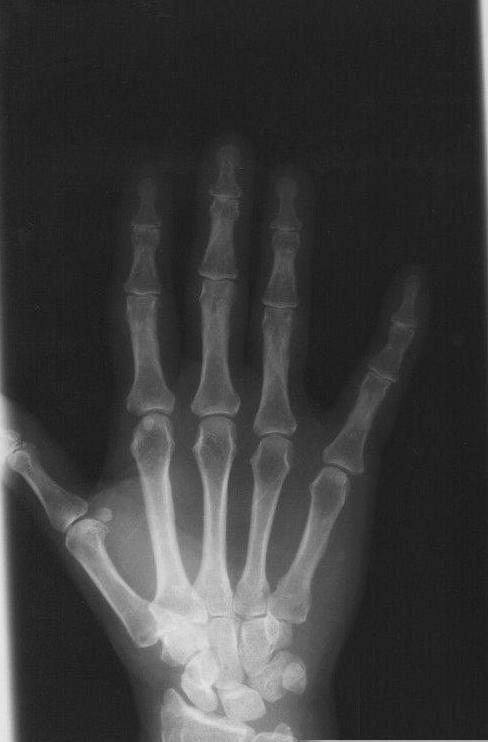

对于骨折的病人,如果说骨折断端 疼痛消失,不一定是骨折的痊愈,因为在骨折两周以后,骨折断端瘀血、肿胀会慢慢吸收消退,而且骨折断端会有纤维连接的生成,这个时期的骨折部位疼痛感会减轻甚至消失,但是骨折的部位还不稳定,所以说骨折并没有完全痊愈。我们所说的愈合,一定要经过x光片,看到有连续性骨痂形成,达到我们临床愈合的标准才能说是痊愈。

局部无压痛、纵向叩击痛,无异常活动,x光片显示有连续性骨痂通过骨折线,骨折线已消失或接近消失。